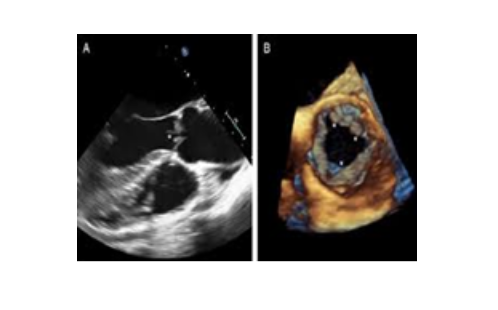

3. Siêu âm tim 3D, 4D

Khác với siêu âm 2D, khi hình ảnh thu được theo không gian 2 chiều, tức là trên 1 mặt phẳng (lát cắt), đầu dò siêu âm 3D, 4D các tinh thể áp điện theo ma trận, để thu được hình ảnh siêu âm theo không gian 3 chiều (hình khối), gọi là siêu âm 3D. Nếu có thêm chiều chuyển động (chiều thời gian) thì ta có siêu âm 4D.

Siêu âm tim 4D cung cấp hình ảnh sinh động, toàn diện, dễ hình dung hơn siêu âm 2D, đặc biệt quan trọng trong các bệnh lý sau: van động mạch chủ, van hai lá (nhất là trong kỹ thuật mitraclip: kẹp van hai lá bị hở mà không cần phẫu thuật), thông liên nhĩ, đánh giá thất trái...